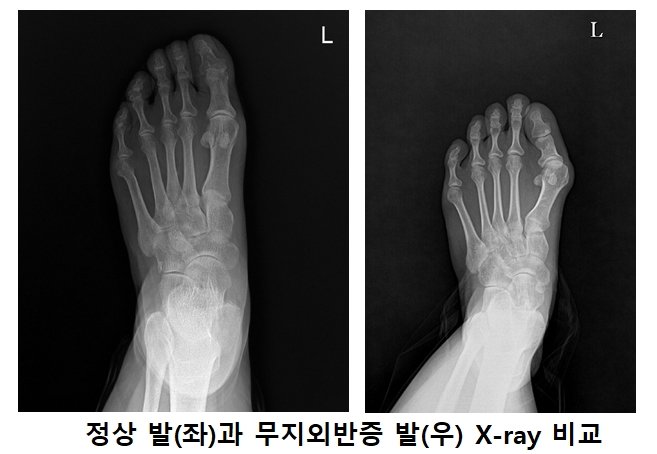

샌들같은 발가락이 노출되는 신발을 신으면서 신경 쓰이는 질환이 있다. 바로 무지외반증이다. 엄지발가락인 무지가 새끼발가락 쪽으로 휘어가는 질환이다. 내측 돌출 부위가 신발에 반복적으로 마찰되면서 통증과 염증을 유발한다. ‘하이힐 병’이라고 불릴 만큼 하이힐처럼 볼이 좁고 굽이 높은 신발을 장시간 착용하면 생기는 질환으로 알려져 있다. 하지만 평발이나 가족력 등 유전적인 요인이 원인인 경우도 많다. 건강보험심사평가원 통계자료에 따르면 2023년 무지외반증으로 병원을 찾은 환자는 5만 4665명으로, 이중 약 81%가 여성이었다.

무지외반증을 간과하면 안 되는 큰 이유는 치료하기 전까지 엄지발가락의 변형이 계속 진행되기 때문에 조기치료가 무엇보다 중요하고 비수술적 치료로는 완치가 어렵다는 점이다. 무지외반증은 증상이 진행될수록 발뿐 아니라 튀어나온 엄지발가락 내측 볼의 통증으로 보행이 정상적이지 않아 무릎이나 허리 등에 통증이 발생할 수 있다. 장기간 방치할 경우 발목인대 손상과 무릎 관절염, 허리 디스크 등 2차 질환으로 이어질 수도 있다.

무지외반증의 주요 증상으로는 볼이 좁은 신발을 신기가 어려워지고 엄지 관절 부위 통증이 발생한다. 통증으로 걷기가 불편하고 증상이 심한 경우 관절 탈구, 엄지 관절 부위 관절염이 발생할 수도 있다. 증상이 심하지 않은 초기라면 발가락 사이에 보조기를 끼거나 교정 깔창 등을 이용한 보존적 치료를 시행한다.

걷기가 힘들 정도로 통증이 심하거나 다른 합병증이 왔다면 수술을 받는 것이 좋다. 방치 시 엄지발가락에 실릴 체중이 분산되면서 다른 발가락에 부담이 가중되면서 합병증이 유발되기도 하고, 무지외반각이 40도 이상의 중증 변형일 경우 수술 방법이 복잡해지며 수술 이후의 재발 확률도 높아질 수 있다.